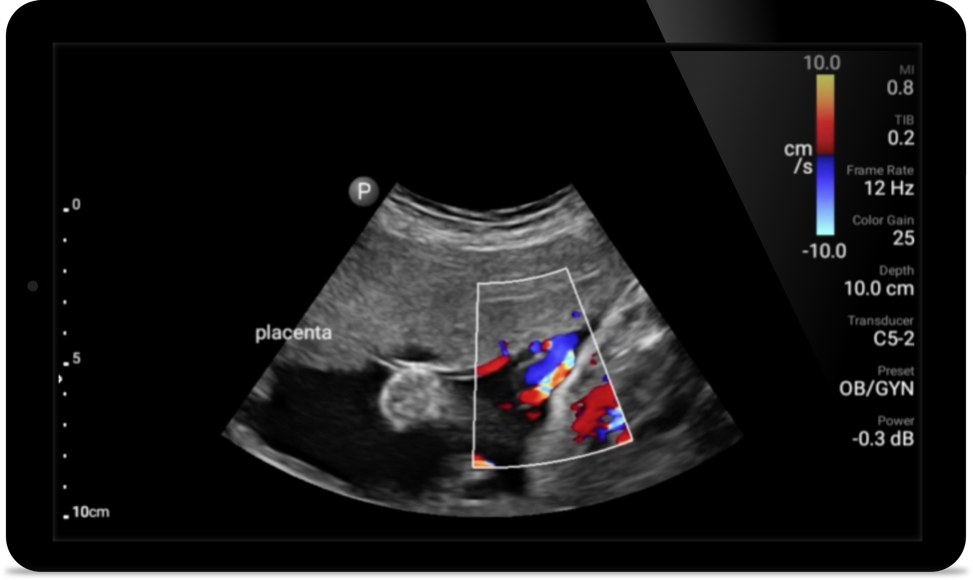

Transductores Lumify para medicina interna

Transductor de matriz lineal de banda ancha Lumify L12-4

• Rango extendido de frecuencias de operación entre 12 y 4 MHz • Tamaño de apertura: 34 mm • 2D, Doppler orientable a color, Modalidad M, XRES avanzado e imágenes armónicas multivariables, SonoCT • Imágenes de alta resolución para aplicaciones superficiales: tejidos blandos, vasculares, superficiales, musculoesqueléticos y pulmonares • Marcador de línea central • Transductor USB-C con cable reemplazable